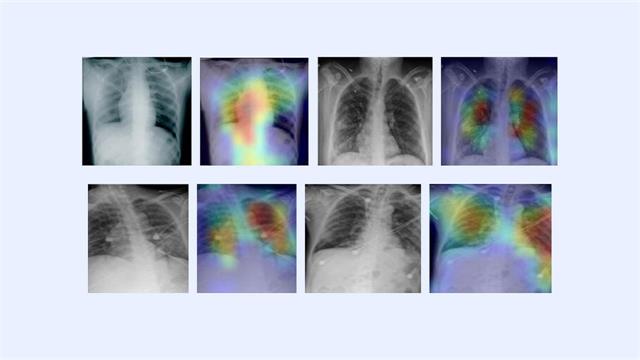

Η τεχνική χρησιμοποιεί τεχνολογία ακτίνων-X συγκρίνοντας σαρώσεις με βάση δεδομένων 3.000 εικόνων ασθενών με COVID-19, υγιών και ανθρώπων με πνευμονία.

Στη συνέχεια χρησιμοποιώ μια διαδικασία τεχνητής νοημοσύνης και  ένας αλγόριθμος φτάνει στη διάγνωση.

Κατά το εκτεταμένο διάστημα δοκιμής, η τεχνική αποδείχτηκε περισσότερο από 98% ακριβής.